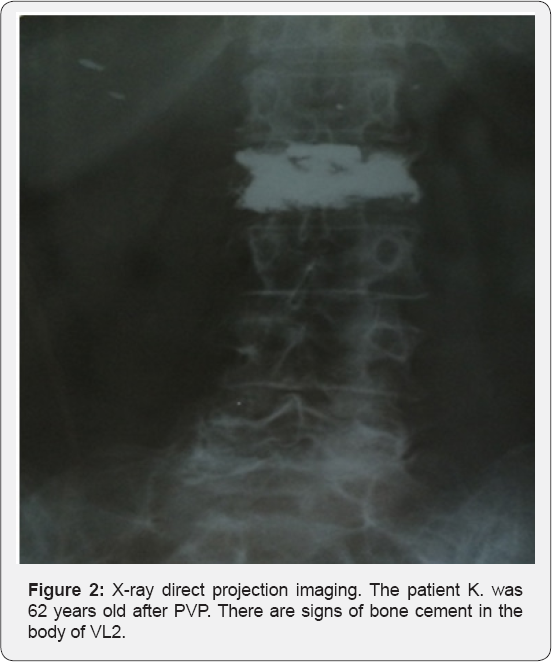

A total of 41 patients (36 females and 5 males) met the inclusion criteria and were treated with PVP and then included in the follow-up program that is still going on. The total number 74 percutaneous vertebroplasty was performed in 41 patients with traumatic compression fractures of vertebral bodies of the I and II degree. Of these 41, 5 participants were male (12%) and 36(88 %) were female; the average age of the patients was 66 years (range, 55-78 years). The average operative time was 51.2 ±4.2 (range, 34-55)min. The average cement volume was 4.5 ± 0.54 (range, 3.4-6.0)ml. The mean follow-up was 16.0 ± 4.2 (range, 12-24) months. The evaluation of the results of treatment was carried out according to the following criteria: dynamics and severity of pain syndrome prior and after percutaneous vertebroplasty, motor activity of the patient, and dependence on analgesics. All patients achieved substantial pain relief after surgery. The VAS score decreased significantly from a preoperative value of 8.4 ± 1.2 to a post-operative value of 2.0 ± 0.2 and was maintained at 2.2 ± 0.4 at the final follow-up (p < 0.01). The extravasation of cement into the venous plexuses was noted in 1 patient, which was the reason of occlusion of small branches of the pulmonary arteries, and clinical presentations of this case was asymptomatic. No other complications were encountered. All patients were able to sustain rapid mobilization within 12- 24h after procedure, and the mean hospitalization length after PVP was 3.5 days (range 3-5). The long- term results revealed that all patients had significantly improved mobility, and by the end of the first postoperative month and mainstay during following 24 month, there were not any subsequent vertebral fractures. In additionally, during the follow up period the majority of patients reported that decreased usage pain relief medicines or not used (Figure 1 & 2).